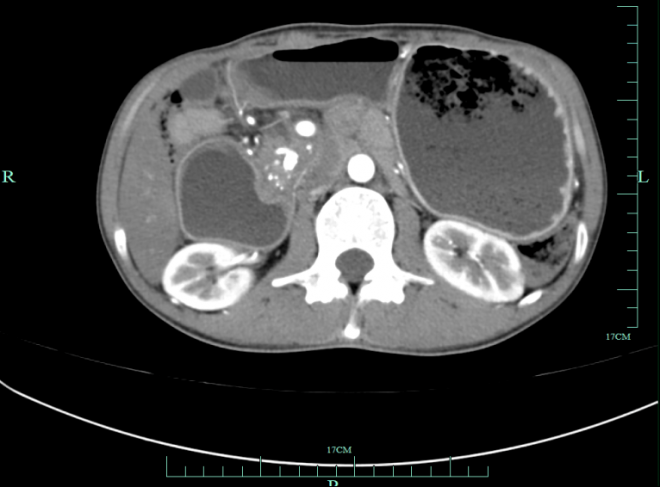

趙磊的腹部CT顯示胰頭異常,考慮腫瘤病變的可能。年紀輕輕怎麼會得腫瘤呢?就在趙磊以為結果可能弄錯了的時候,核磁、病理穿刺等各項檢查指向了同一個結果——「胰腺癌」。